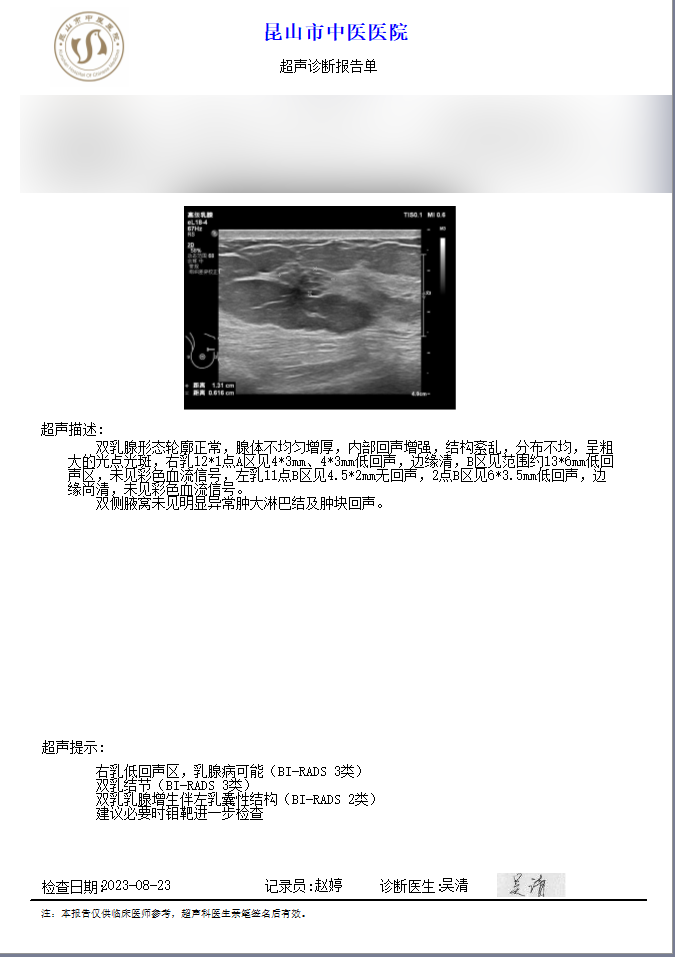

这里有一个病例分享给大家:40岁的谢女士,23年4月门诊发现双乳3类结节,边缘清晰,建议每半年复查B超评估,2023年患者按期行B超复查,2024年未进行复查,2025年复查时结节边缘欠光整,形态欠规则,且有少许血流信号,评估为4A类,收入我院甲乳外科行乳房肿块穿刺活检,病理提示双乳均为早癌,已行根治手术,目前规律治疗中。

▲23年4月

▲23年8月

▲2025年